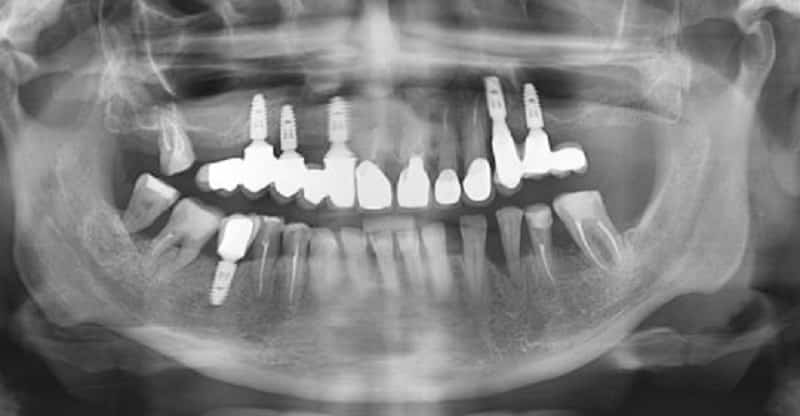

На данном этапе также выполняются детальные исследования челюстной области с использованием трехмерной томографии и ортопантомографии — панорамной рентгенографии.

Эти исследования важны для выявления заболеваний и аномалий, которые могут быть не заметны при обычном осмотре. В первую очередь это касается кист и гранулем. Кроме того, врач анализирует размеры костной ткани и особенности строения челюсти, что позволяет тщательно спланировать предстоящую операцию.

Период адаптации новых тканей может занять до трех месяцев или даже больше. Также существует метод, позволяющий устанавливать импланты в челюсть без предварительного наращивания костной ткани. Хотя этому способу всего около десяти лет, он уже пользуется большой популярностью. Специальные материалы и оборудование позволяют устанавливать зубные импланты (см. фото выше) на минимальном количестве костной ткани даже при отсутствии всех остальных зубов. При этом не имеет значения состояние кровообращения в десне, время приживления значительно сокращается, а стоимость процедуры становится ниже благодаря уменьшению затрат на материалы и оборудование.